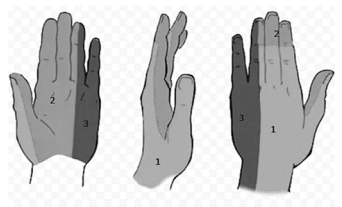

Uma paciente de 50 anos de idade, obesa, com diabetes e hipotireoidismo, queixa-se de sensação de parestesias há dois meses nas regiões de número 2 e 3, conforme a imagem, sobretudo quando acorda pela manhã. Com base nessas informações, é correto afirmar que os nervos afetados são, respectivamente,